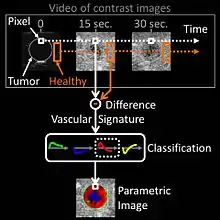

Microbubbles-based contrast media is administered intravenously into the patient blood stream during the ultrasonography examination. Due to their size, the microbubbles remain confined in blood vessels without extravasating towards the interstitial fluid. An ultrasound contrast media is therefore purely intravascular, making it an ideal agent to image organ microvasculature for diagnostic purposes. A typical clinical use of contrast ultrasonography is detection of a hypervascular metastatic tumor, which exhibits a contrast uptake (kinetics of microbubbles concentration in blood circulation) faster than healthy biological tissue surrounding the tumor.[65] Other clinical applications using contrast exist, as in echocardiography to improve delineation of left ventricle for visualizing contractibility of heart muscle after a myocardial infarction. Finally, applications in quantitative perfusion[66] (relative measurement of blood flow[67]) have emerged for identifying early patient response to anti-cancerous drug treatment (methodology and clinical study by Dr. Nathalie Lassau in 2011[68]), enabling the best oncological therapeutic options to be determined.[69]

In oncological practice of medical contrast ultrasonography, clinicians use 'parametric imaging of vascular signatures'[70] invented by Dr. Nicolas Rognin in 2010.[71] This method is conceived as a cancer aided diagnostic tool, facilitating characterization of a suspicious tumor (malignant versus benign) in an organ. This method is based on medical computational science[72][73] to analyze a time sequence of ultrasound contrast images, a digital video recorded in real-time during patient examination. Two consecutive signal processing steps are applied to each pixel of the tumor:

- calculation of a vascular signature (contrast uptake difference with respect to healthy tissue surrounding the tumor);

- automatic classification of the vascular signature into a unique parameter, the latter coded in one of the four following colors:

- green for continuous hyper-enhancement (contrast uptake higher than healthy tissue one),

- blue for continuous hypo-enhancement (contrast uptake lower than healthy tissue one),

- red for fast hyper-enhancement (contrast uptake before healthy tissue one) or

- yellow for fast hypo-enhancement (contrast uptake after healthy tissue one).

Once signal processing in each pixel is completed, a color spatial map of the parameter is displayed on a computer monitor, summarizing all vascular information of the tumor in a single image called a parametric image (see last figure of press article[74] as clinical examples). This parametric image is interpreted by clinicians based on predominant colorization of the tumor: red indicates a suspicion of malignancy (risk of cancer), green or yellow – a high probability of benignity. In the first case (suspicion of malignant tumor), the clinician typically prescribes a biopsy to confirm the diagnostic or a CT scan examination as a second opinion. In the second case (quasi-certain of benign tumor), only a follow-up is needed with a contrast ultrasonography examination a few months later. The main clinical benefits are to avoid a systemic biopsy (with inherent risks of invasive procedures) of benign tumors or a CT scan examination exposing the patient to X-ray radiation. The parametric imaging of vascular signatures method proved to be effective in humans for characterization of tumors in the liver.[75] In a cancer screening context, this method might be potentially applicable to other organs such as breast[76] or prostate.